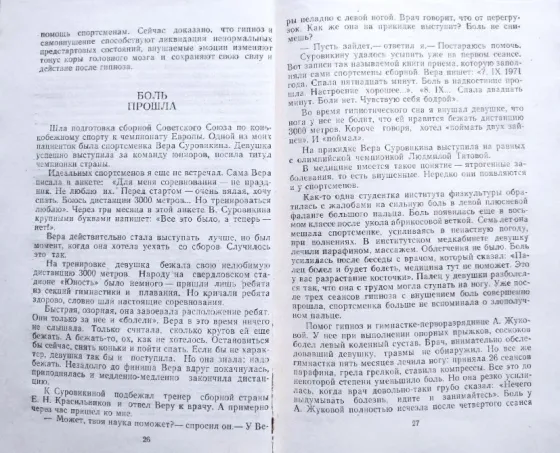

Psychology and Psychiatry_Book Selection

Delivery from Almaty

1. Hypnosis without sensations – V.V. Kuzmin, 1982, “Kazakhstan”, soft cover, pp.: 80, format:...

July 11

7

7